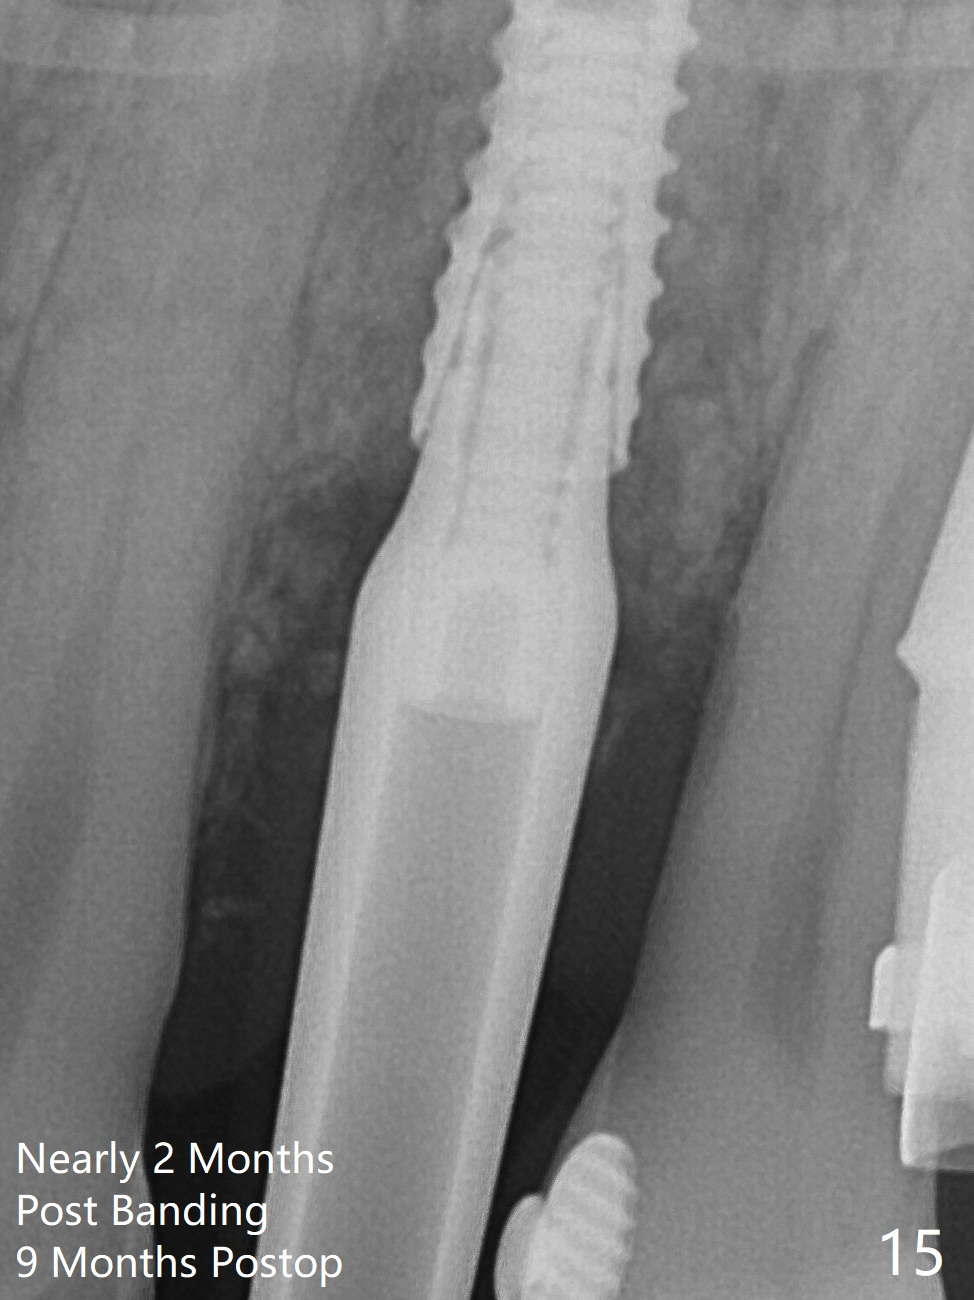

A few days prior to surgery, the tooth #12 developed abscess, self controlled by water pik (Fig.1 *). The buccal plate is defective. Initial osteotomy is close to the root of the tooth #11 (Fig.2). After adjustment of the trajectory and the depth of osteotomy (Fig.3), a 3.8x15 mm dummy implant is placed (Fig.4,5). In spite of a shorter implant (3.8x13 mm) placed deeper, approximately 7 mm implant threads are not covered buccally by the native bone (Fig.6 red dashed line). If the implant were placed deeper, the crown/implant ratio would become more unfavorable (abutment screw loosening, Fig.7). Since a mill abutment (4.5(2) mm) is inserted before Vanilla Graft, the deepest portion of the socket is unfilled (Fig.7 *). With meticulous use of a long explorer and additional allograft, the space is closed (Fig.8 *). The buccal plate collapses with apparently fistula formation 2 months postop. The patient removes the provisional for cleaning. It appears that the mill abutment is buccally placed and needs heavy reduction. The mill abutment is loose 2 months 10 days postop. When it is retightened, it tilts distal. Bone remains around the implant 6 months postop (Fig.9). Without a provisional at #12 for 5 months, the tooth #13 appears to have been shifted mesially (Fig.10 arrow). The mill abutment at #12 changes to a healing one. A lingual button is placed in the mesial surface of #13. Splinted provisional is fabricated with supraocclusion at #14 and 15 as an anchor (implants). The tooth #13 is being distalized with power chains. Limited ortho is finished nearly 2 months post banding (Fig.15,16).